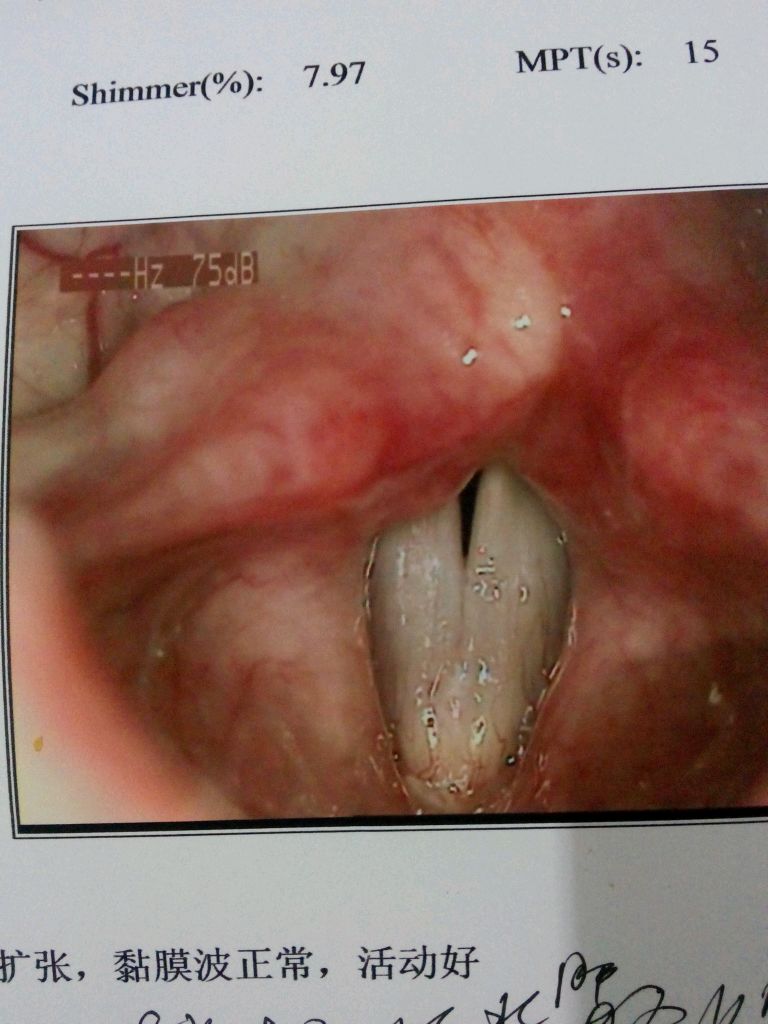

如题,看过无数的医生,吃过无数药,水肿和肥厚还是没有好,现在说一句话都觉得要耗尽全身的力气,希望亲们能帮我指点一下迷津阿!

这张显示的是闭合不全……

你声带是慢性水肿肥厚,恢复有点慢,需要耐心。长期吃中药。

没有什么问题 适当的做做科学发音训练就有利于声带的闭合